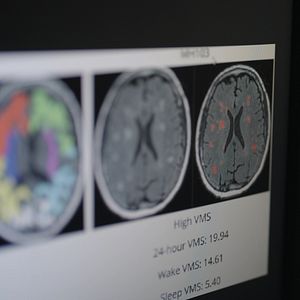

Trotz der Tatsache, dass etwa die Hälfte der Weltbevölkerung die Menopause durchlebt und viele Frauen unter teils stark belastenden Beschwerden leiden, ist diese Lebensphase weiterhin unzureichend erforscht. Historische Vorurteile haben über Jahrhunderte dazu geführt, dass Betroffene ihre Symptome häufig still ertrugen, was die Wissenslage bis heute beeinträchtigt. Internationale Forschungsteams versuchen nun, die Folgen des sinkenden Östrogenspiegels auf Körper und Gehirn besser zu verstehen. Zudem wird untersucht, wie Menopause-Symptome mit Depressionen und dem erhöhten Alzheimer-Risiko von Frauen zusammenhängen. Parallel dazu suchen Wissenschaftlerinnen und Wissenschaftler nach möglichen Ansätzen, um diesen Auswirkungen entgegenzuwirken.